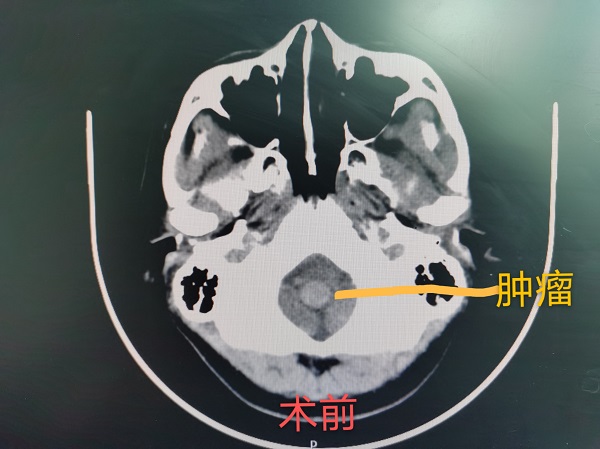

近日(ri),神經(jing)外科(ke)成(cheng)功完成(cheng)我(wo)院第30例腦幹腫瘤切除術(shù)。該患者爲(wei)一(yi)名(míng)37歲的(de)女性,因左側肢體(ti)活動(dòng)障礙入院治療,術(shù)中(zhong)見腫瘤位于(yu)延髓內(nei)部(bu),伴有(yǒu)出血,龐克軍主(zhu)任在(zai)顯微鏡下清(qing)除血腫,同時分(fēn)塊切除腫瘤,手術(shù)順利,術(shù)後(hou)患者肢體(ti)活動(dòng)恢複良好,按期出院。

自2017年(nian)總醫(yī)院成(cheng)功開展(zhan)第一(yi)例腦幹腫瘤手術(shù)以(yi)來,随着神經(jing)外科(ke)顱底顯微神經(jing)外科(ke)技(ji)術(shù)不斷(duan)成(cheng)熟,近幾年(nian)随着全國(guo)醫(yī)保聯(lian)網工(gong)作(zuò)的(de)推進(jin),外地來院就診的(de)腦幹腫瘤及(ji)複雜病例不斷(duan)增多(duo),腦幹腫瘤手術(shù)風險高(gao)、時間長(zhang),但昰(shi)在(zai)顯微神經(jing)外科(ke)技(ji)術(shù)成(cheng)熟的(de)前(qian)提下,随着神經(jing)內(nei)鏡咊(he)定向導(dao)航等(deng)新(xin)技(ji)術(shù)的(de)應用(yong),總醫(yī)院神經(jing)外科(ke)手術(shù)的(de)安(an)全性得到(dao)了(le)充分(fēn)保障。